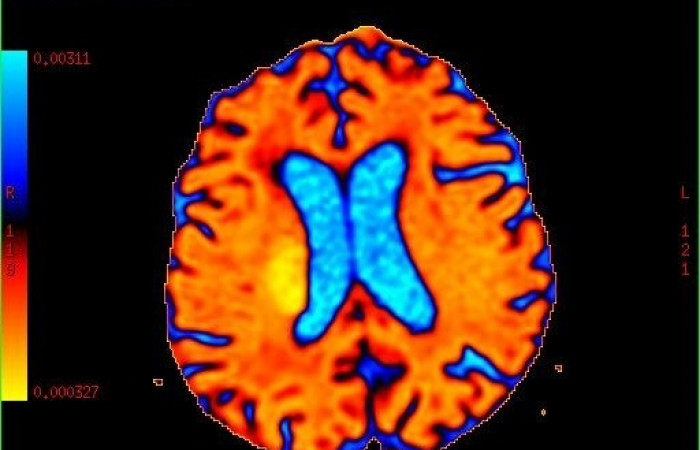

- obrazowanie perfuzji mózgu,

ˇ badanie perfuzyjne mózgu (z i bez środka kontrastowego)